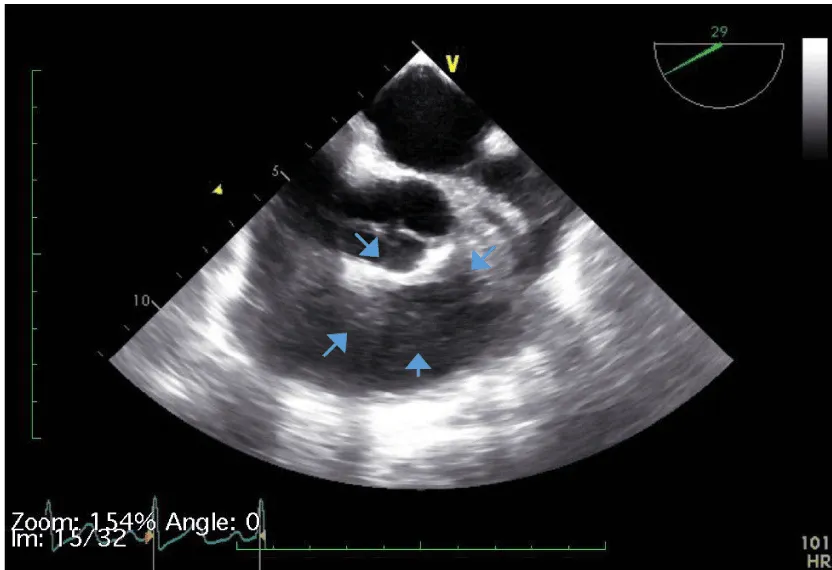

Her initial vital signs upon presentation to the hospital were; blood pressure: 161/76 mm Hg, heart rate: 96 beats per minute, respiratory rate: 27 breaths per minute. Physical exam revealed a cardiac auscultation findings of a grade 2 diastolic murmur which was loudest at the 2nd right intercostal space as well as a grade 2 systolic flow murmur. Cardiac biomarkers were elevated with initial troponin-I of 0.33 ng/mL, peak of 2.28 ng/mL and subsequent down trend. Electrocardiography (Figure 1) showed sinus rhythm with anterior and inferolateral T wave inversion and chest radiograph (Figure 2) was unremarkable. She underwent coronary angiography which revealed normal coronary arteries. The takeoff of the right coronary artery (RCA) was noted to be superior and anterior to its normal position (Figures 3A and 3B). Transthoracic and transesophageal echocardiography (TEE) revealed normal left ventricular systolic function and severe insufficiency of the aortic valve with Quadricuspid morphology (Figure 4A in Diastole, Figure 4B in Systole, Figure 4C Long Axis of the aortic valve). She underwent aortic valve replacement with a # 19mm ON-X mechanical valve. Intraoperatively it was noted that the ostium of the right coronary artery was over the aberrant leaflet. Her postoperative course was complicated by the development of supraventricular tachycardia, posteriorly localized pericardial effusion, severe hemolytic anemia, renal failure and pancreatitis leading to her death eleven days after the surgery.

Figure 4a: QAV in diastole (arrows pointing to 4 cusps).

The diagnosis of QAV was facilitated by TEE, which revealed the characteristic findings. The short axis views of the aortic valve are optimal for making the diagnosis of QAV. The classic X shaped commissural aortic valve pattern in diastole (Figure 4B) compared to the Y shape of a trileaflet valve is diagnostic (Figure 4D) [3].